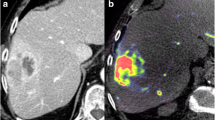

The Figure presents an exemplary case of a patient undergoing DEB-TACE. Pre-interventional CT (a) and VPCT (c) show a hypervascularized tumor in Segment 8 of the liver with increased blood volume, blood flow and arterial liver perfusion. Corresponding, b shows demarcation of a HCC lesion with increased intra-tumoral parenchymal blood volume (PBV) in the C-arm CT acquisition. d-f present the corresponding imaging techniques after successful DEB-TACE. e shows complete reduction of PBV in the PBV maps and typical staining of contrast media within the lesion in the overlaid non-enhanced C-arm CT acquisition